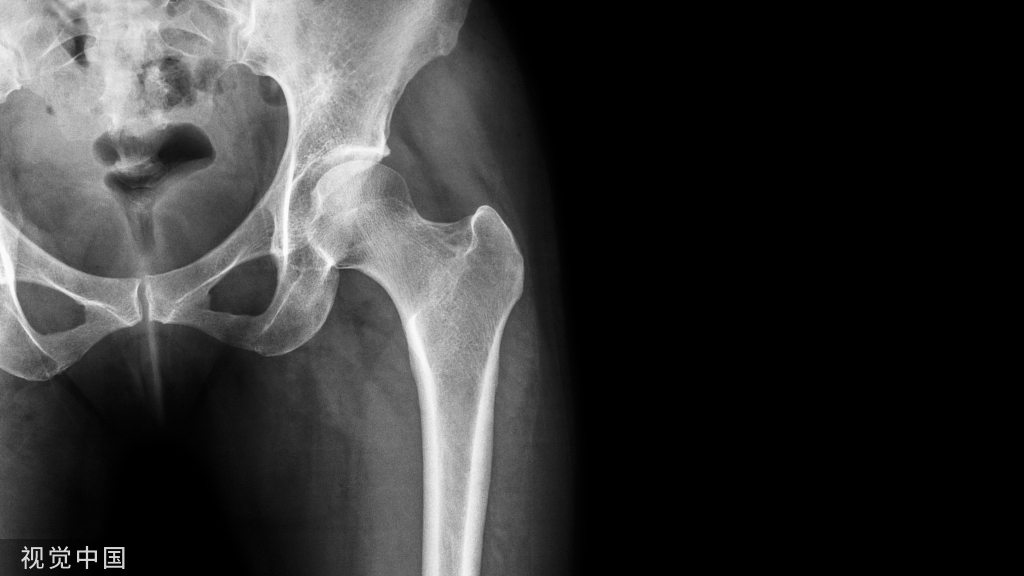

关于T1DM和T2DMO之间的差异,更具体地说是关于两种疾病在代谢紊乱中骨脆性的病理生理学,已经有大量的研究进行证实:T1DM是一种以T细胞介导的β细胞破坏为特征的自身免疫性疾病。由于T1DM的发病通常发生在儿童期和青春期,骨量的累积受到影响,导致炎症、胰岛素缺乏和胰岛素样生长因子-1(IGF-1)水平降低,引起骨量和骨矿化程度降低。在T2DM的早期虽与T1DM相比骨损害表现不太明显,但随着病程的进展,血糖控制越来越差,糖尿病骨折的风险也显著增加。与T1DM和T2DM的慢性高血糖相关的一个共同因素是骨组织材料特性的改变,这与临床中常见的绝经后骨质疏松引发的骨折类型有较大的差异。